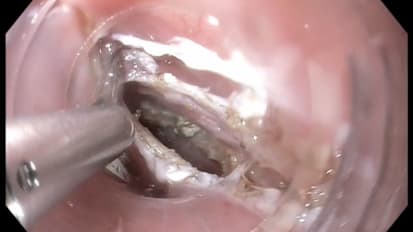

Z-POEM (Diverticulotomy for Zenker’s diverticulum) Video

Z-POEM (Diverticulotomy for Zenker’s diverticulum)